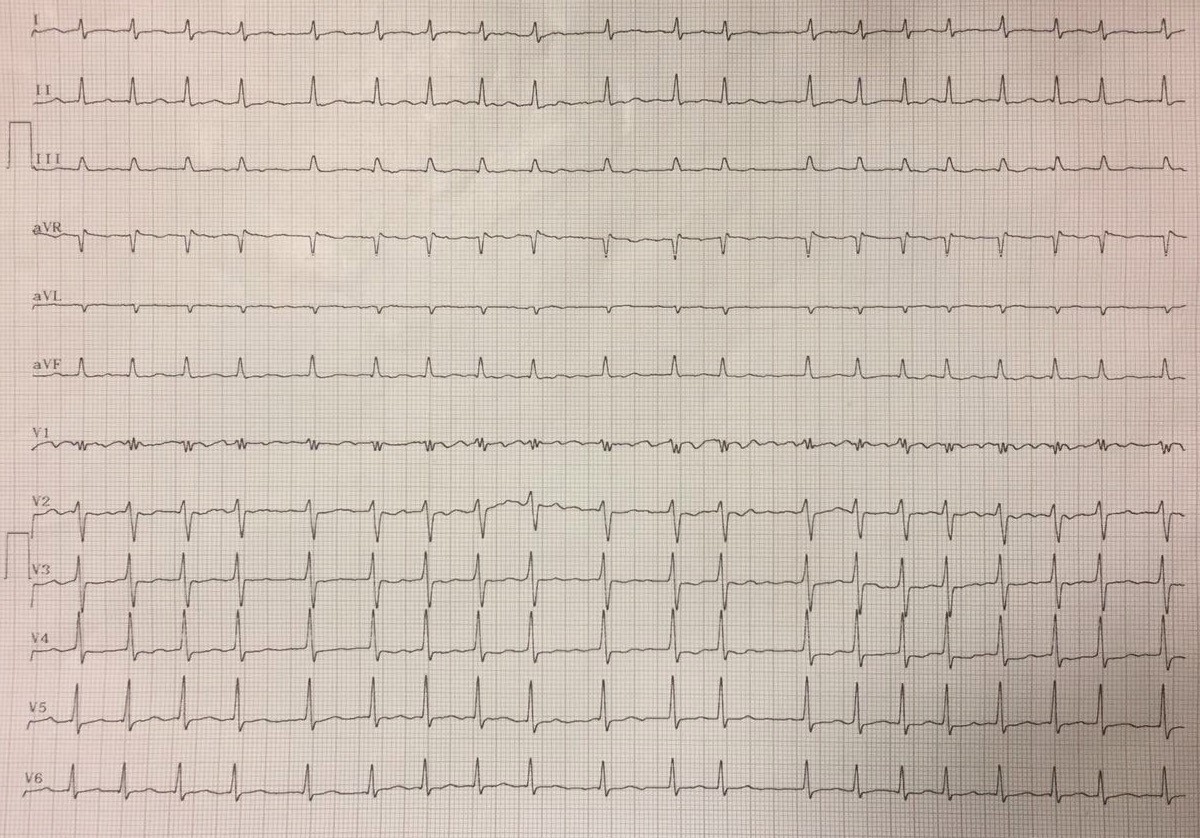

Essa página tem o intuito de trazer semanalmente ECGs novos e reais da prática clínica para estimular você a colocar em prática tudo o que sabe sobre ECG!

Está pronto para o Desafio?